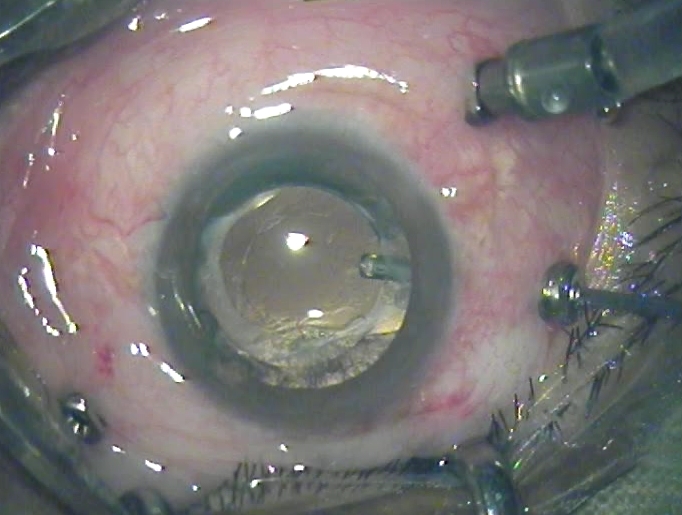

'''3포트 유리체 절제술''': 3개의 작은 포트를 만들어 유리체 젤에 접근하여 제거한다.

유리체 절제술은 복잡한 망막 박리를 치료하기 위해 사용되는 수술법이다.[4] 특히 크기가 크거나 쉽게 보이지 않는 망막 열공에 유용하며, 망막 박리 후 발생할 수 있는 망막의 흉터 조직 성장인 증식성 유리체 망막병증에도 사용된다.[4][23][24] 이 기술에서는 망막에 가해지는 당기는 힘을 완화하기 위해 눈에서 유리체 젤을 제거한다.[4][10] 망막 뒤의 모든 액체는 배액되고 열공은 냉동 또는 레이저로 밀봉된다.[4][10] 제거된 유리체는 이후 망막을 안정시키는 가스 방울 또는 실리콘 오일로 대체된다.[4][10][25] 가스 방울로 치료받은 환자는 엎드린 자세를 유지하고 항공 여행, 고고도 및 스쿠버 다이빙을 삼가도록 권장된다.[4][10][25][26] 실리콘 오일로 치료받은 환자는 오일을 제거하기 위해 후속 수술이 필요하다.[4][10][26] 이전에 백내장 수술을 받지 않은 환자의 경우, 유리체 절제술은 치료받은 눈에서 백내장이 발생할 위험을 증가시킨다.[4][10][26]